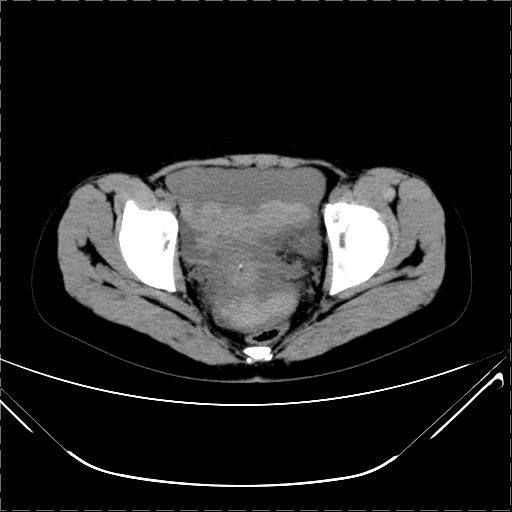

女 29岁 突然腹部疼痛1天 b超示子宫左后方肿块。月经正常。

影像表现复杂,膀胱上见一囊性包块,比膀胱密度高,其内有不均匀稍高密度,似与道格拉斯窝肿物无分界,病灶没有张力,因其腹平坦,推定其具有流动性,但又似见包膜,而b超没有报告这一现象。确实没见过。考虑卵巢囊肿蒂扭转并囊内出血可能。

病变主要位于道格拉斯窝,而且大体形态比较扁平且贴合子宫直肠,无明显张力及对周围脏器压迫,所以考虑为液体,而中间可见囊样病变伴环形强化,期内还可见分隔影,结合突发急性腹痛故多考虑囊腺瘤伴破裂出血。

腹腔镜术后 卵巢黄体囊肿破裂出血